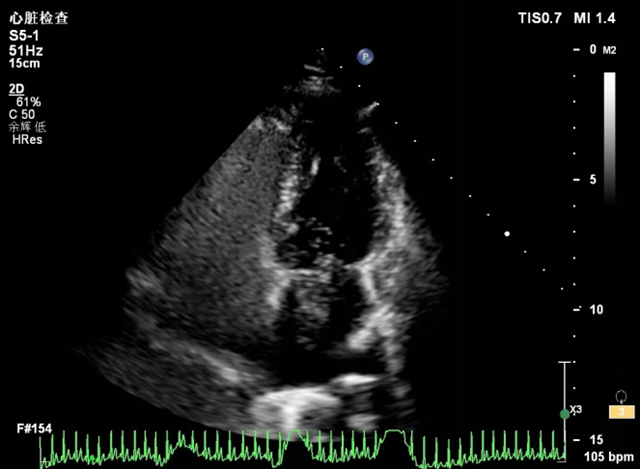

为明确诊断,张同学到超声影像科做了右心声学造影(发泡试验)进一步检查,结果显示:推入造影剂后第3个心动周期开始大量“小泡”,自右心房经房间隔中份卵圆孔处进入左心房,确诊卵圆孔未闭。

卵圆孔未闭(PFO)是不明原因脑卒中、偏头痛、矛盾性栓塞等的病因之一,右心声学造影是诊断卵圆孔未闭的有力工具。

右心声学造影是一项简便易行的超声心动图检查方法。一般通过肘正中静脉注入振荡后的无菌生理盐水,使右心系统显影,再通过联合超声心动图检查,就可以进一步了解右心系统各腔室的解剖和血流状况,协助确定有无心腔内(卵圆孔未闭、房间隔缺损等)或心腔外(肺动静脉瘘等)的右向左分流。